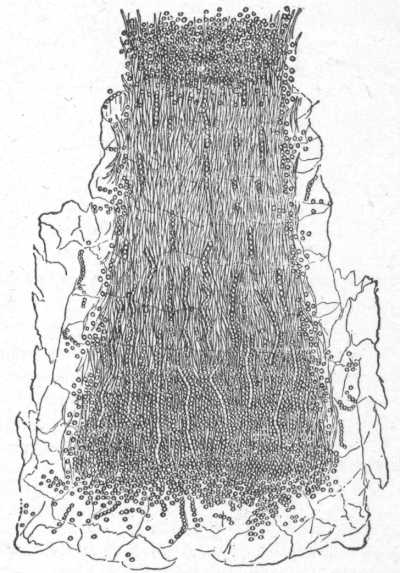

Fig. 7.

A normal sebaceous gland in connection with a lanugo hair. (After Neumann.)

a, Capsule; b, fatty secretion; c, h, secreting cells; d, root of lanugo hair; e, hair-sac; f, hair-shaft; g, acini of sebaceous gland.